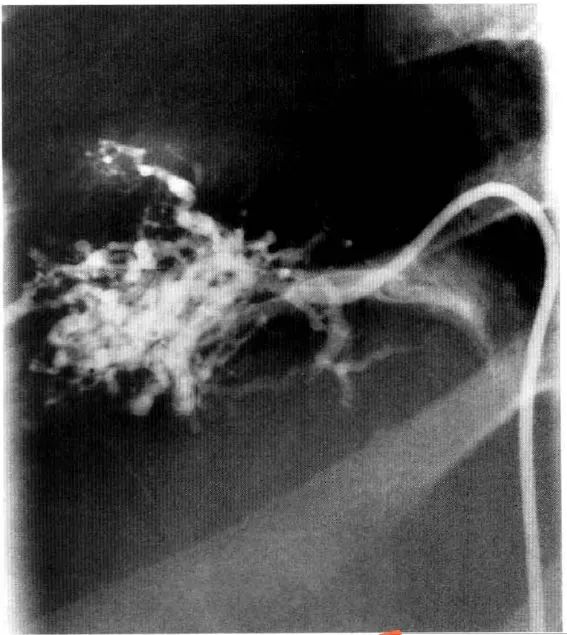

静脉造影是诊断该病的「金标准」。其典型表现为静脉狭窄、不规则,可在肝静脉汇入下腔静脉处或静脉入口远端发现血栓。代偿性的肝静脉表现为典型的「蜘蛛样」改变,也可见肝内侧支和再通静脉。

图2 BCS患者的肝静脉造影,注意「蜘蛛样」表现(来源:见参考文献[6])